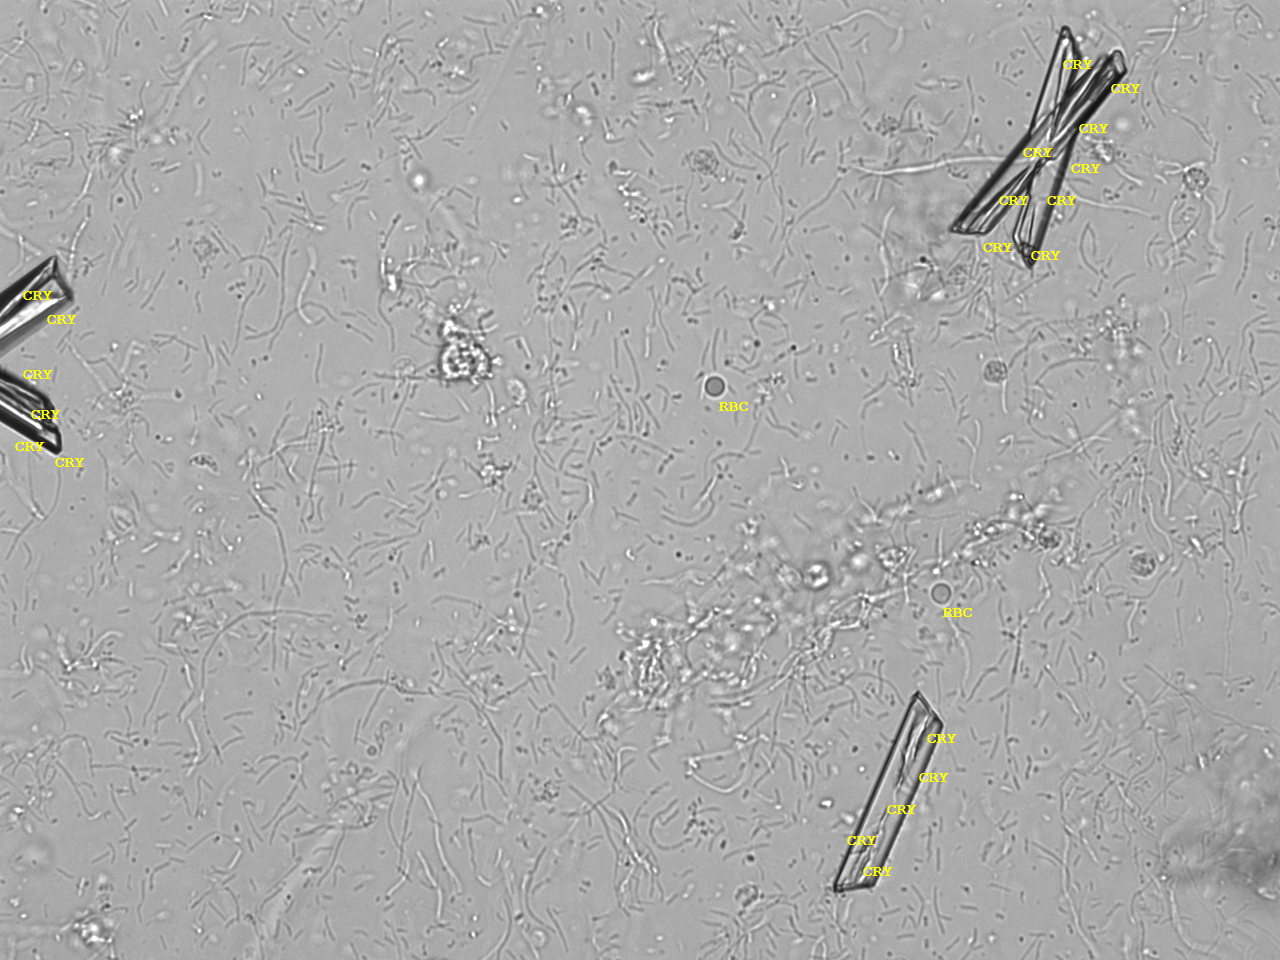

Urin-Feature: CaPhosphate